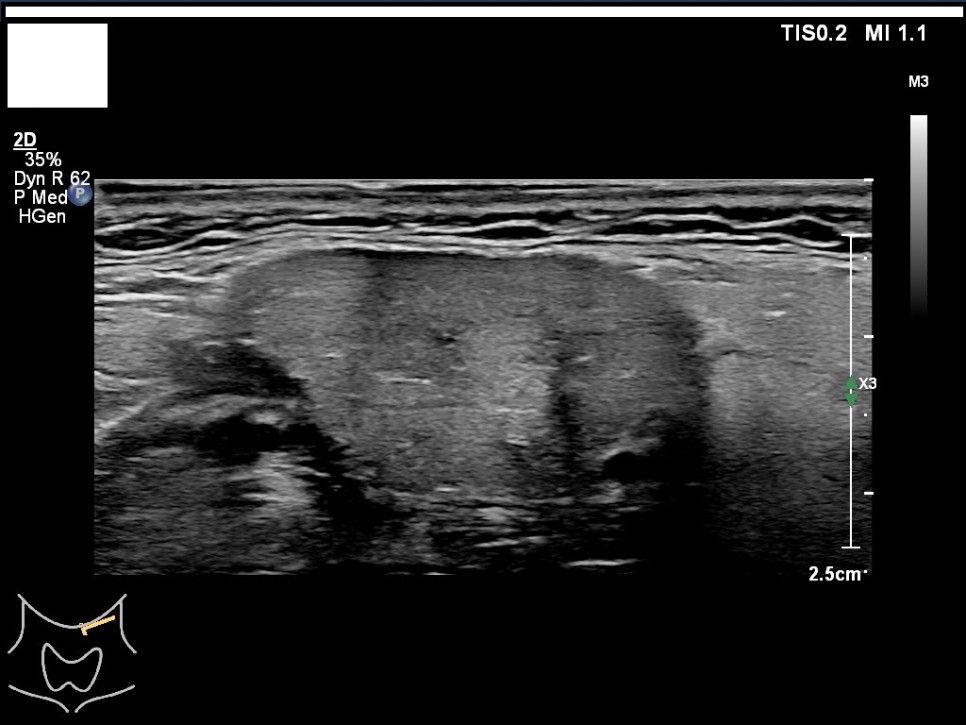

갑상선, 부갑상선 초음파 검사 급여 기준 1. 표준 영상의 범위 모든 영상에는 경부의 해부학적 위치(모식도나 문자)를 표기하여야 한다.

A) 병변이 없는 경우: 우엽 중부 가로 스캔, 우엽 중앙부 세로 스캔, 협부 가로 스캔, 좌엽 중부 가로 스캔, 좌엽 중앙부 세로 스캔, 우경부 림프절, 좌경부 림프절 나) 병변이 있는 경우: 병변이 없는 경우의 표준 영상과 함께 병변 부위에서 2개의 수직 관계 단면 영상(횡단/종단) 및 병변의 크기가 측정된 경우: 병변이 없는 경우의 표준 영상

좌경부 림프절 5/우엽 중부 가로 스캔/우엽 중앙부 세로 스캔

우경부림프절/좌엽중앙세로 스캔/좌엽중앙가로스캔

좌측 경부 림프절 / 중심 경부 림프절 / 협부 옆 스캔 2. 판독 소견서가) 등록 번호, 성명, 생년월일 또는 연령, 성별, 검사명, 검사 일시, 판독 일시, 검사와 판독한 의사(면허 번호), 의료기관명, 검사 소견 및 결론 나) 검사 소견에는 갑상선 에코, 병변의 유무를 기술하여야 한다. 결절이 있을 경우 위치, 최대지름, 주요 소견, K-TIRADS의 내용을 기술하여야 하며, 암으로 진단된 결절을 추적할 경우 위치, 3방향 직경, 주요 소견, 전 검사와 변화 여부, 경부 림프절의 평가 및 이상 소견 여부를 기술하여야 하며, 경부 림프절에 이상이 있을 경우 위치, 크기, 주요 소견을 기술하여야 한다. 결절이 여러 개 있을 경우 암 위험도에 따라 선택적으로 기술할 수 있다. 또 소아 등에서의 환자의 협력도 음창 등이 좋지 않아 표준 영상 획득에 제한이 있는 경우 추가 기술해야 한다.